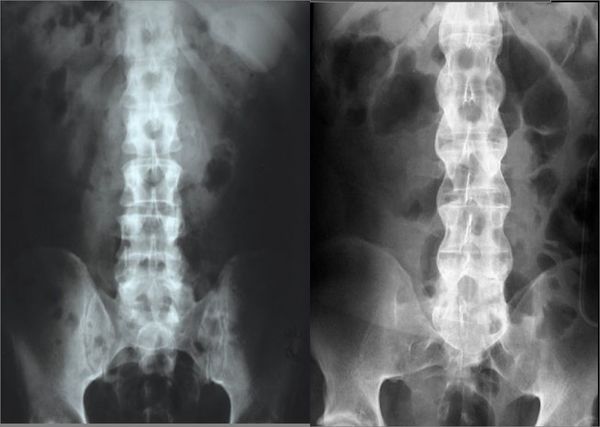

在进行强直性脊柱炎的检查时除了一些常规的检查外,还有一些特殊的强直性脊柱炎的检查方法,对强直性脊柱炎的检查同样有效。那特殊的强直性脊柱炎的检查方法有哪些呢?下面就为大家讲讲特殊的强直性脊柱炎的检查方法。  一般,特殊的强直性脊柱炎的检查方法有:成都强直专科医院

1、电子计算机断层扫描(CT):对于临床怀疑而X线不能确诊者,可以行CT进行强直性脊柱炎的检查。它能清晰显示骶髂关节间隙,便于测定关节间隙有无增宽,狭窄,强直或部分强直有独到之处。蒙兴文

2、磁共振(MRI)和单光子发射计算机断层扫描(SPECT):美国科学家研究了36例患者,24例为炎性下背痛,12例为机械压力所致下背痛的病人。通过标准的X线检查骶髂关节正常.但应用MRI检查:发现54%的炎性下背痛和17%的机械原因性下背痛的患者有骶髂关节炎。这是特殊的强直性脊柱炎的检查方法之一。强直性脊柱炎诊断

3、用SPECT检查:发现38%的炎性下背痛存在骶髂关节炎,而机械原因组无此发现.MRI和SPECT同时检查阳性发现率明显升高。炎性下背痛者58%和机械性下背痛者17%的患者存在骶髂关节炎。因此研究者认为MRI和SPECT闪烁造影骶髂关节拍片,非常有助于强直性脊柱炎的检查,从这个角度讲明显优于普通X线,但费用昂贵,不提倡作为常规检查。这也是特殊的强直性脊柱炎的检查方法。